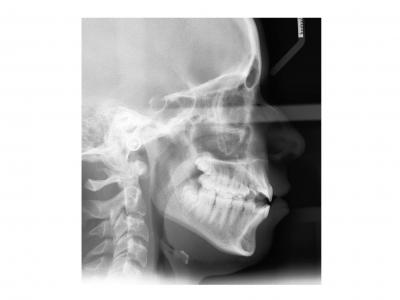

Voici les deux patientes traitées

Ici, dans les deux cas, les deuxièmes prémolaires ont été extraites et les traitements ont duré 18 mois.

Dans le deuxième cas, le désencombrement a fermé les espaces en 6 mois. Les incisives ont été surtorquée pour avoir un meilleur soutien labial. Le traitement qui avait bien débuté, a été difficile à finir, car les anatomies coronaires et radiculaires étaient perturbées.

Si on n'avait pas extrait dans le premier cas, cela imposait une ouverture de l'espace de la 24 et donc une avancée des incisives supérieures et donc une aggravation de la béance. Dans le deuxième, on sortait les racines de l'os alvéolaires (racines déjà apparentes au départ). Même une expansion associée à du stripping et une distalisation des secteurs latéraux n’auraient pas permis de préserver ce parodonte fin.